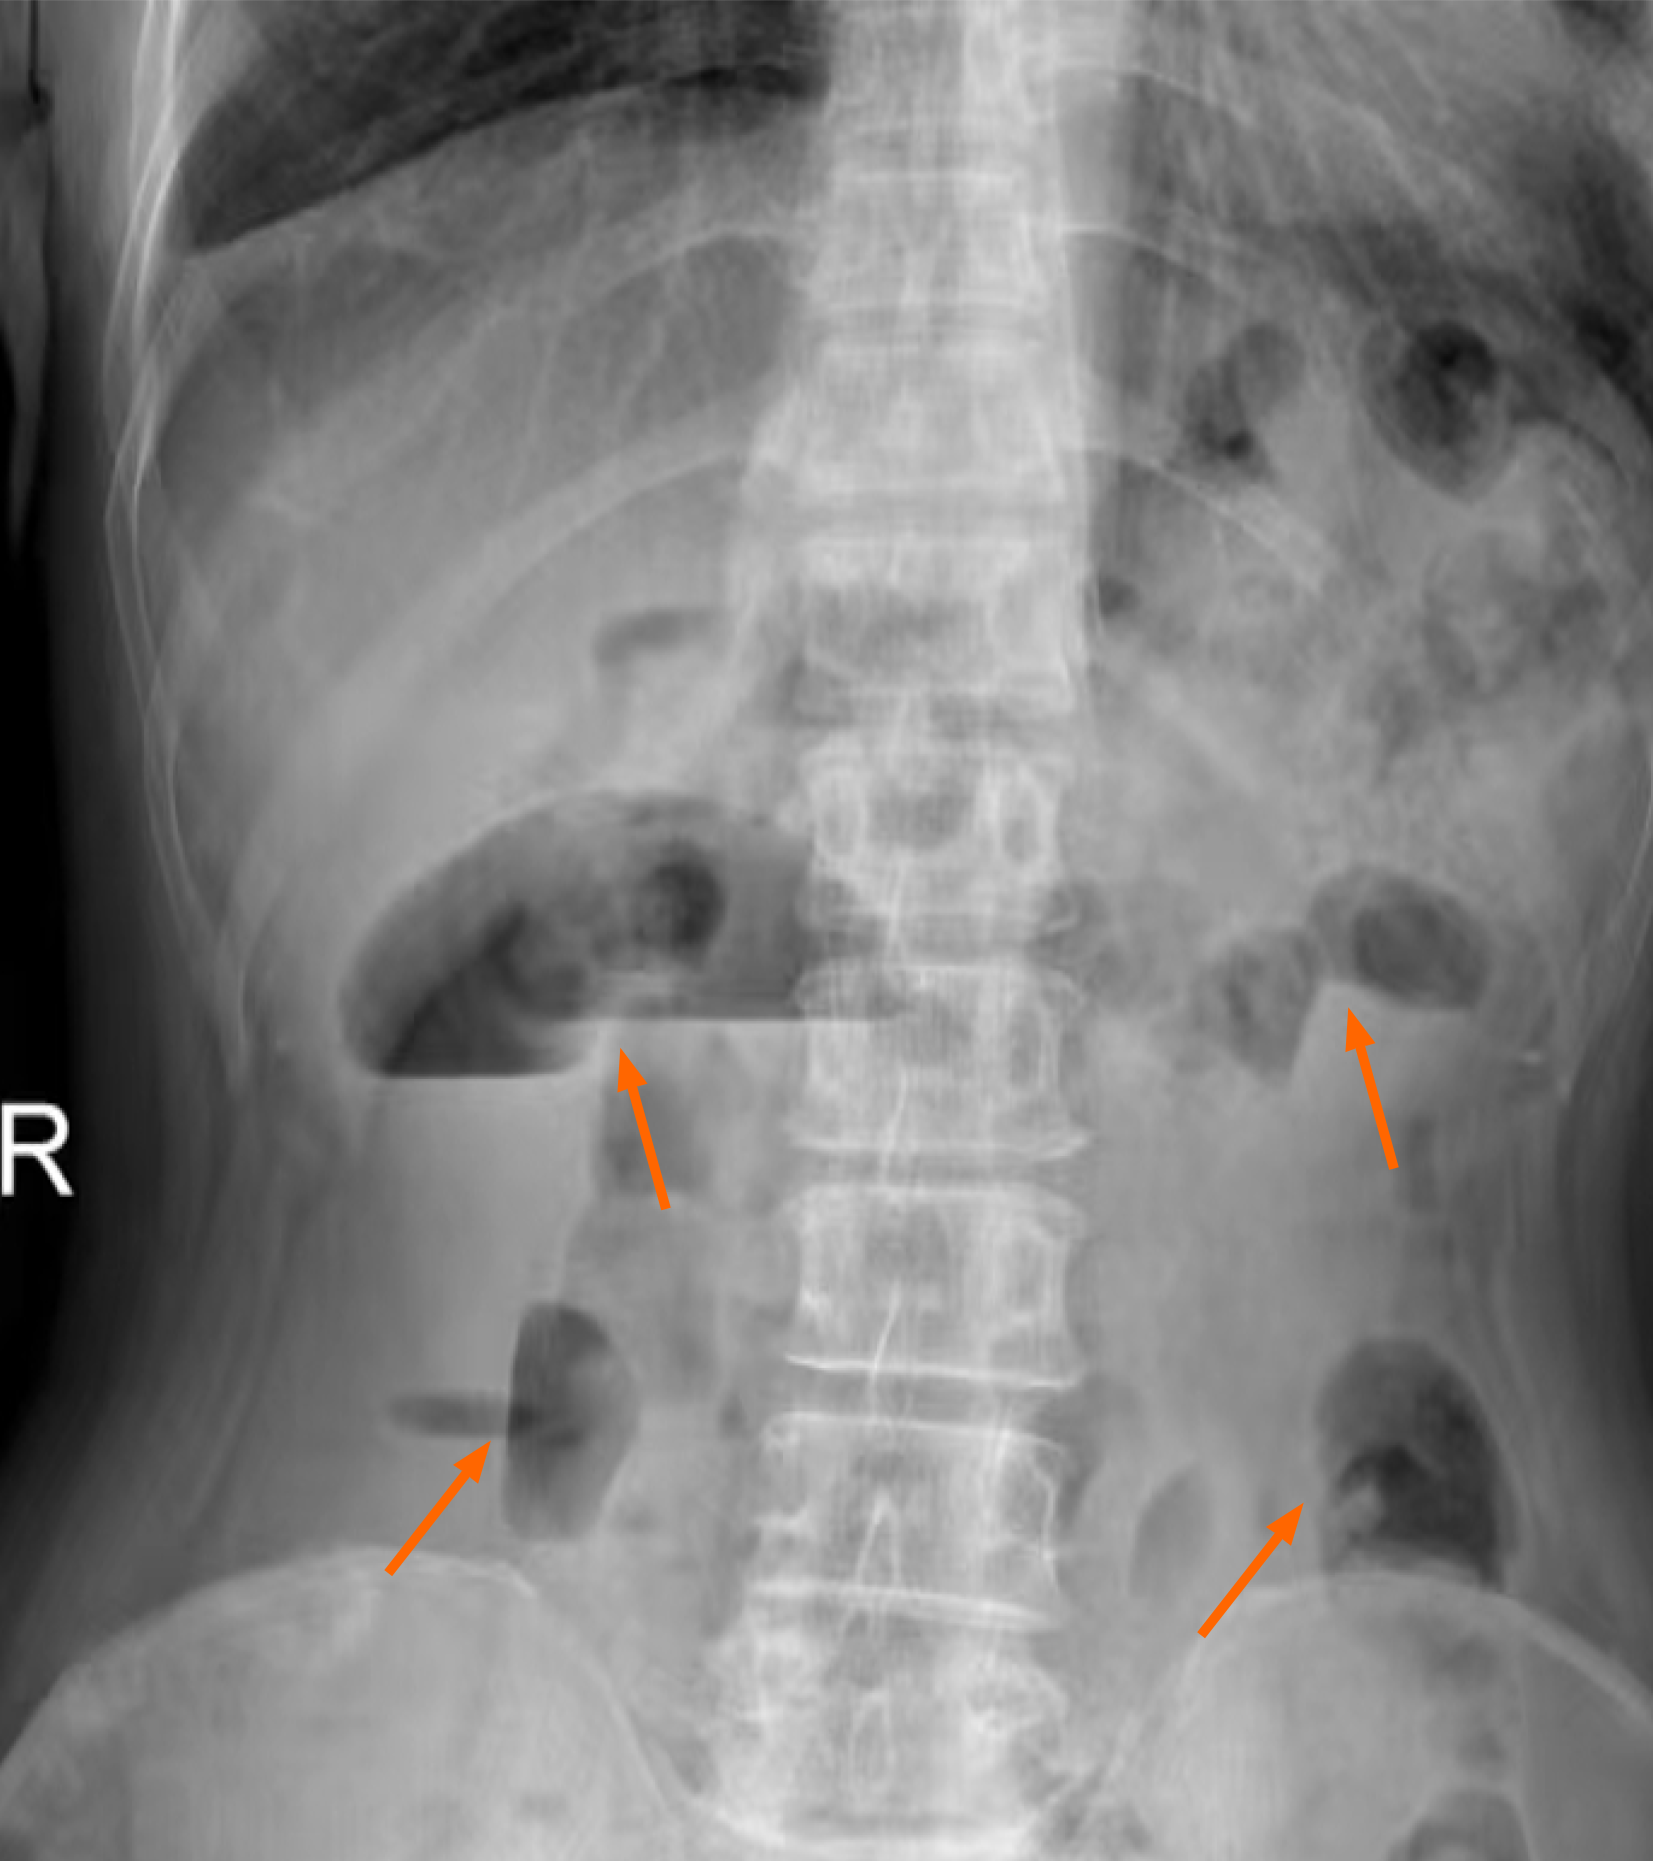

Figure 1

Figure 1 Abdominal upright plain film. Gas accumulation in the abdominal intestine, and scattered fluid levels are seen, indicating intestinal obstruction.

Abdominal upright plain film suggest gas accumulation in the abdominal intestine. Additionally, scattered fluid levels were observed, which illustrates intestinal obstruction (Figure 1). The CT of the chest and abdomen revealed the following findings: Lesions occupied the lower lobe of the left lung, accompanied by pleural hypertrophy in the adjacent pleura; Part of the intestinal tract was dilated, and air-fluid level could be observed in the intestinal ducts, which was considered intestinal obstruction (Figure 2); Multiple slightly enlarged lymph nodes were observed in the right middle and lower abdomen. Worse still, a diverse array of enlarged lymph nodes were observed in the groin bilaterally; An uneven elevation in bone density within the right ilium was suspected to be indicative of bone metastasis.